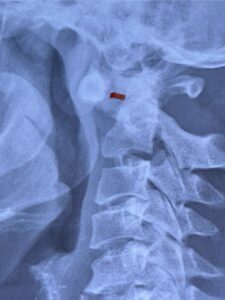

Cervical x-rays revealed a significantly increased atlanto-axial interval (Fig. 5) On review of her imaging studies it was noted that the right C2 isthmus was very thinned by the vertebral foramen (Figs 6a, b, and c) which would make an attempt at placing a C2 pars screw dangerous. A decision was made to perform an occipital-cervical fusion because only possible unilateral fixation and an extensive C1 laminectomy to be performed eliminating a fixation point if a more traditional C1-C2 was performed. Even if C1 lateral mass screws were able to be placed one could only perform a unilateral screw construct fixation to C2. We performed an occipital cervical fusion down to C4 to get enough inferior fixation and C1 laminectomy. The decompression went well. We placed a left unilateral pars screw and bilateral C3 and C4 lateral mass screws. We placed three 12 mm screws in the midline keel (Fig. 7). Postoperatively the patient had all around improvement in her symptoms and did not qualify for rehab. Her post op films at 6 weeks (Fig. 8)

Fig. 6a: Sagittal cervical CT scan demonstrating an abnormally thin right C2 isthmus prohibiting safe placement of screw (red arrow). Notice the vertebral foramen eroding the isthmus bone structure (red dot).